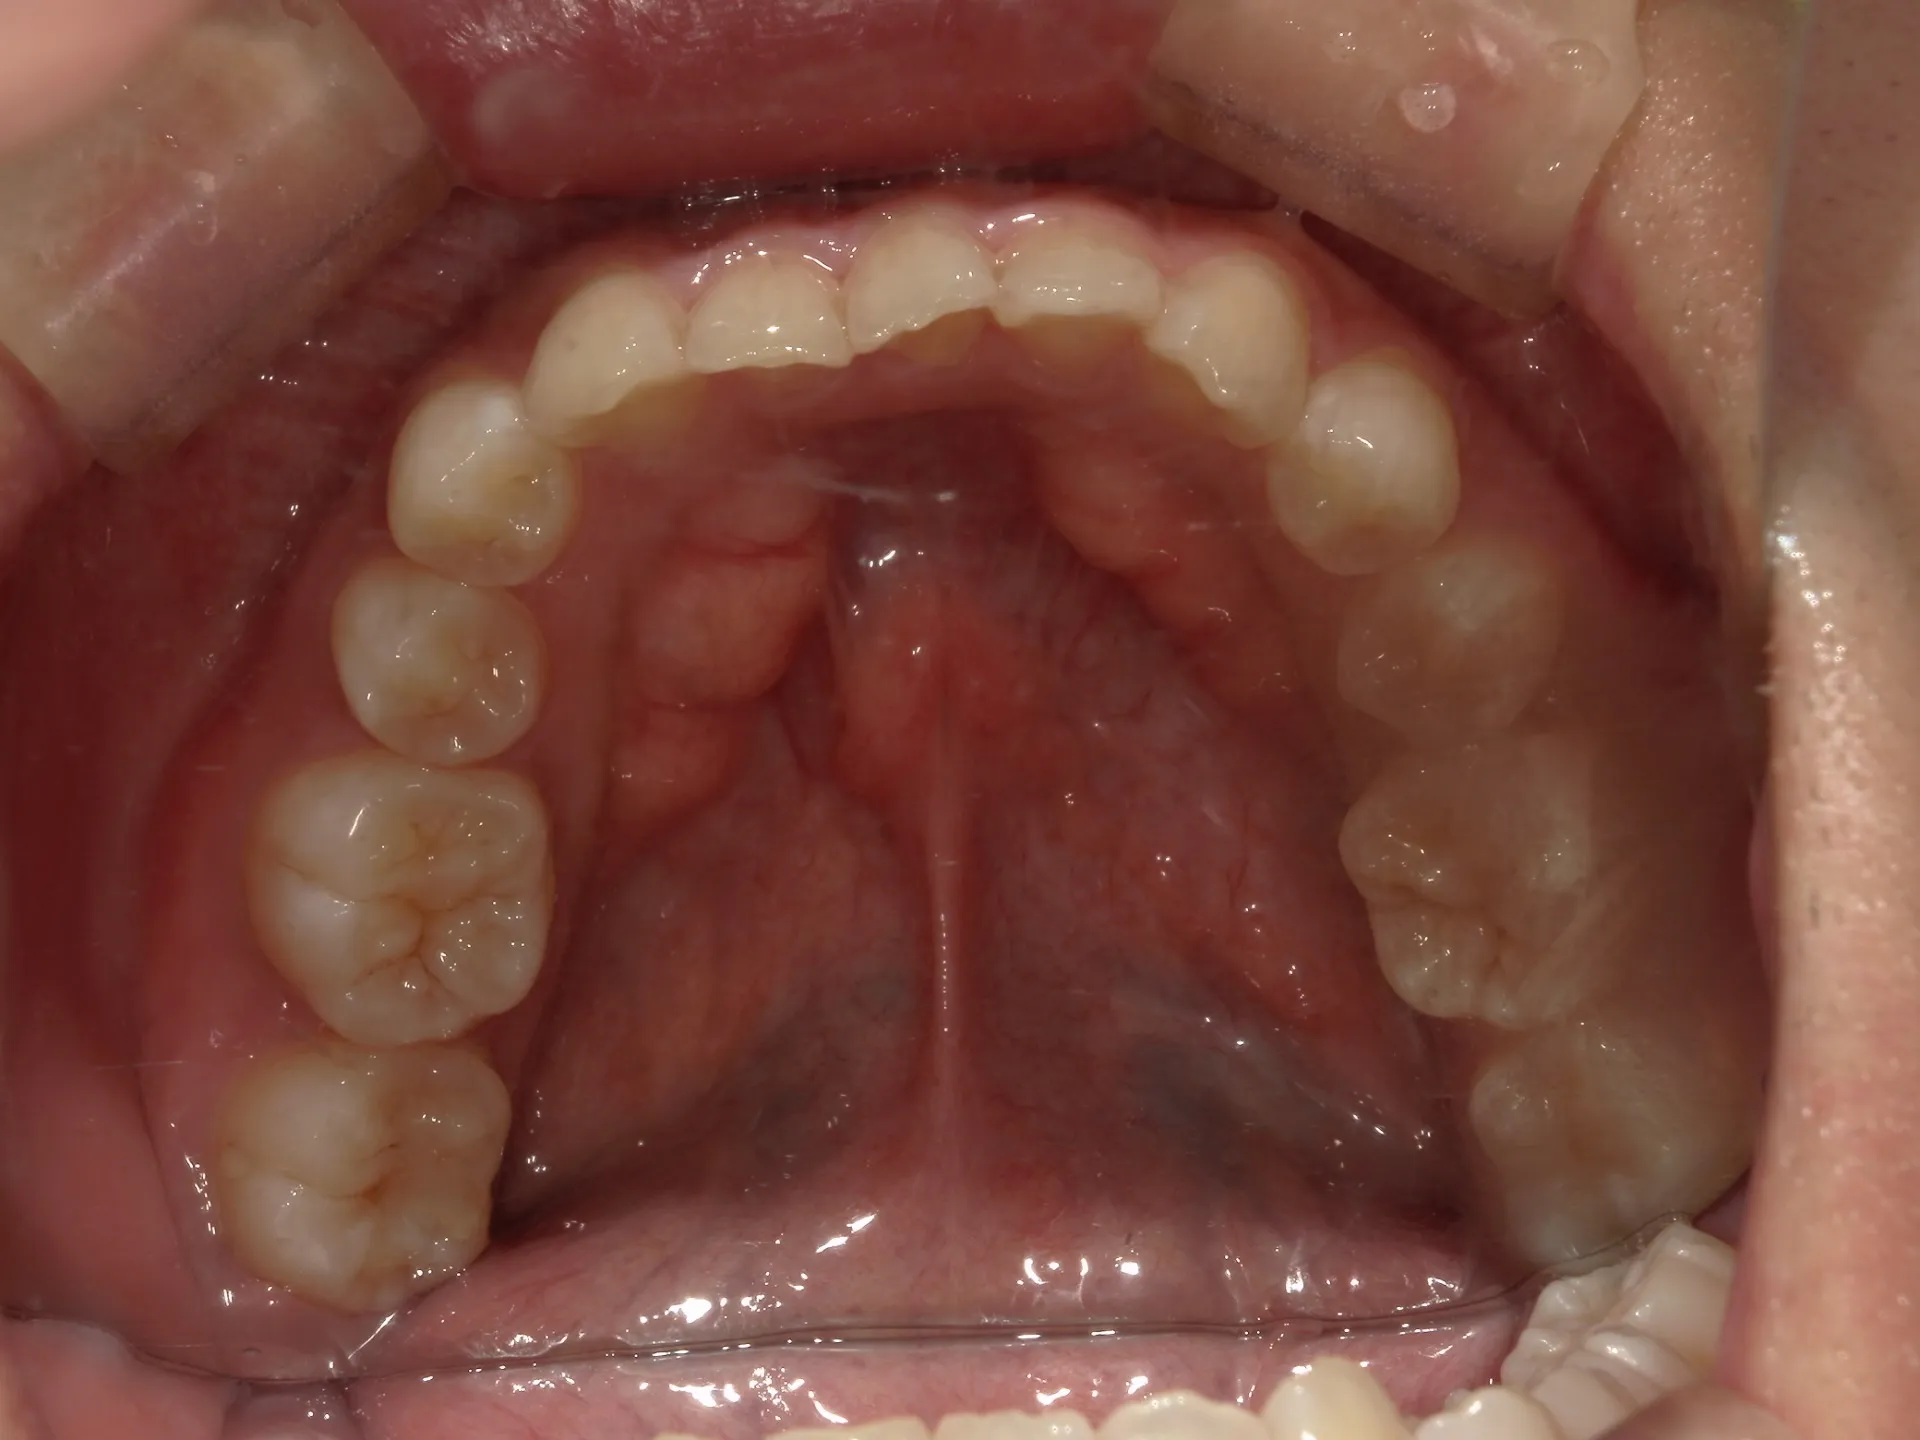

前歯が内側に倒れてたりしませんか?

または2番目の歯が外側に飛び出していませんか?

この2つはよく同時に起こることがあります。

今回はインビザライン矯正治療(マウスピース矯正)で治療した症例についてご紹介いたします。